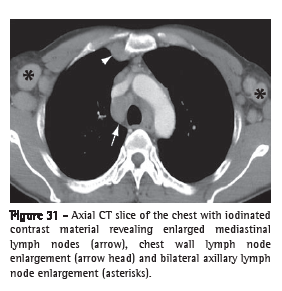

Lymph node enlargement (linfonodomegalia)Lymph node enlargement is characterized by the increase in volume in one or more lymph nodes, due to any cause, surpassing the dimensional limits considered normal for the lymph node chain in question (Figure 31).(52,53) The term "adenomegaly" is not an acceptable synonym, since lymph nodes are not true glandular structures. The term "linfonodopatia" ("lymphatic disease") is reserved for situations in which a disease, such as necrosis, has been identified within a lymph node.